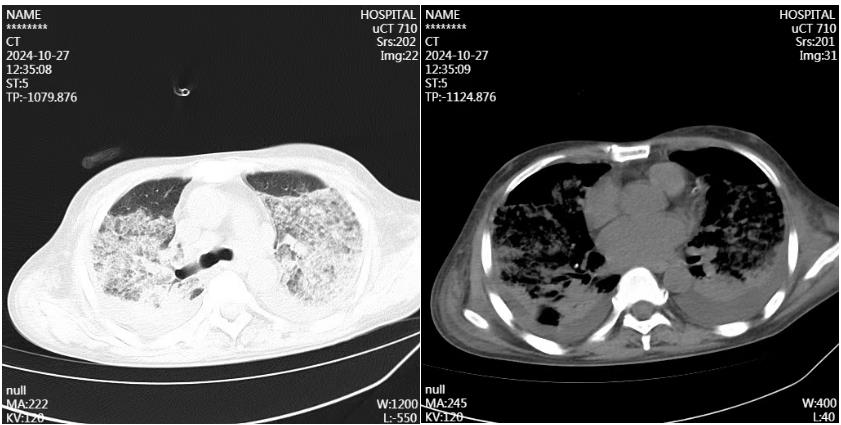

10月27日夜,一名44岁男性患者因发热10余天,呼吸困难7天收治到重症医学科。追问病史,既往体健,无特殊接触史、职业史或旅居史等。此次发病后体温最高39.1℃,于10月20日就诊于当地医院,查血常规示白细胞高达28.16*109/L,胸部CT示双肺渗出,给予吸氧、经验性抗感染治疗。10月23日复查肺部CT示双肺渗出进展迅速,且患者呼吸困难的症状逐渐加重,升级抗生素后仍无效。遂于10月27日到河北大学附属医院就诊。患者入院时极度喘憋,面罩吸氧条件下脉搏氧饱和度仅仅79%,氧合指数65mmHg,CT示双肺大量渗出伴实变——“大白肺”,面对随时危及生命的严重低氧血症,值班医师田煜坤立即给予经口气管插管、机械通气。然后迅速建立了中心静脉通路并进行床旁超声检查评估心肺功能。

10月17日胸部CT